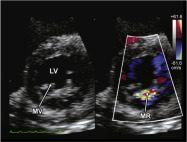

| 5.5. Cửa sổ siêu âm cạnh ức (video 73) Mặt cắt trục dài cạnh ức Phóng đại (Zoom) hình ảnh van hai lá | ![]() | Dòng Doppler màu tại: Van hai lá (MV) Nhĩ trái (LA) Thất trái (LV)

| ||||